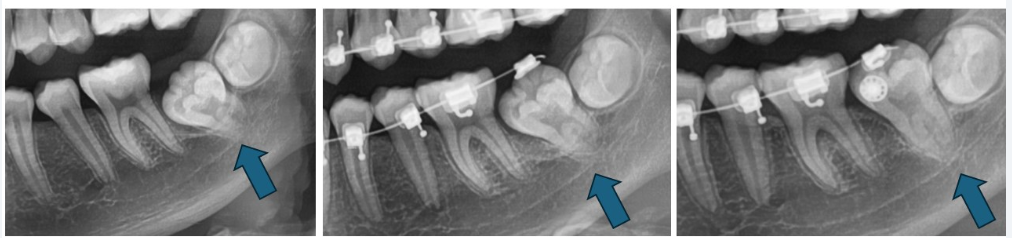

從這三張 X 光圖可以清楚看到牙齒的位置變化:

1️⃣ 初診階段(左圖)

第二大臼齒斜斜地卡在骨頭裡,沒有空間自行萌發。

2️⃣ 中期治療(中圖)

我們先透過雷射把牙齒露出來,並黏上矯正器。

再用矯正的力量,一步一步把牙齒往上移動,讓它慢慢移到正常位置。

3️⃣ 後期進展(右圖)

牙齒已經拉到接近正常位置,牙根也保持得很好。再調整一下角度和咬合,就能完成矯正治療。